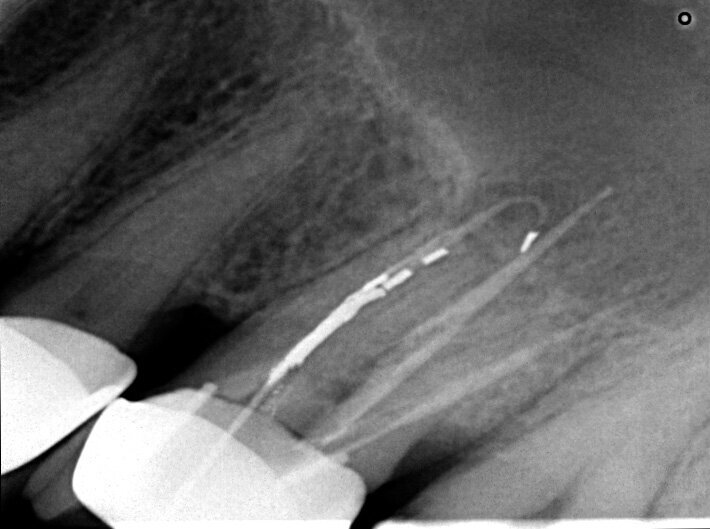

Un patient avait été adressé au cabinet en raison de problèmes associés à la fracture d’une lime. Il était pilote de ligne et se plaignait d’écoulements nasaux purulents lorsqu’il était en vol. La radiographie pré-opératoire (Fig. 1) a distinctement montré la présence de deux fragments d’une lime fracturée dans les canaux mésiaux et d’un cône traversant l’apex de la racine palatine. Après l’imagerie CBCT avec iCAT, il est apparu clairement que le sinus gauche était presque totalement rempli de liquide inflammatoire (Fig. 2) et que le cône présent dans le canal palatin pénétrait dans le sinus. Sur l’image de reconstruction multi planaire (MPR), nous pouvions également distinguer les deux fragments de lime fracturée dans les deux canaux mésiaux (Figs. 3 et 4) et aussi un autre fragment dans le sinus sans aucun contact avec le canal (Fig. 5). L’utilisation de différents filtres nous a permis de visualiser les fragments de lime (Figs. 6–9), ainsi que l’inflammation et le fragment de lime fracturée à l’intérieur du sinus. Nous avons également mieux perçu la position du cône qui émergeait du canal palatin et pénétrait dans le sinus.